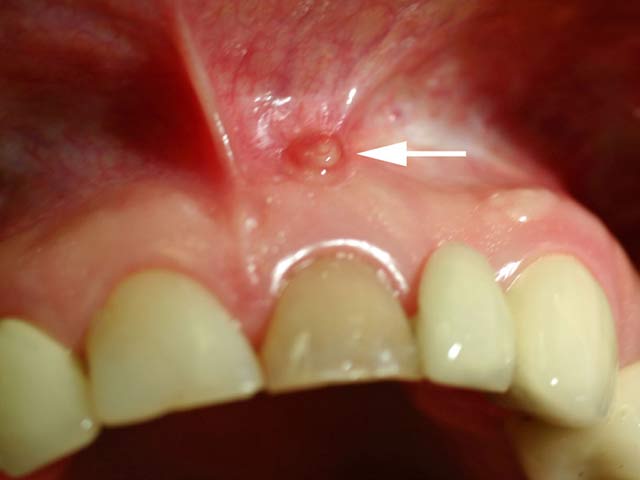

- Δημιουργία συριγγίου κοντά στο προβληματικό δόντι

- Εκροή πύου και απόστημα δοντιού

Τα συνήθη συμπτώματα μιας αποτυχημένης ενδοδοντικής θεραπείας είναι ο πόνος, ο οποίος μπορεί να εμφανίζεται κατά τη μάσηση ή κατά τη λήψη ζεστών ή κρύων ροφημάτων. Σε άλλες περιπτώσεις μπορεί να παρουσιαστεί πρήξιμο ή ακόμη και συρίγγιο στην περιοχή κοντά στο προβληματικό δόντι.